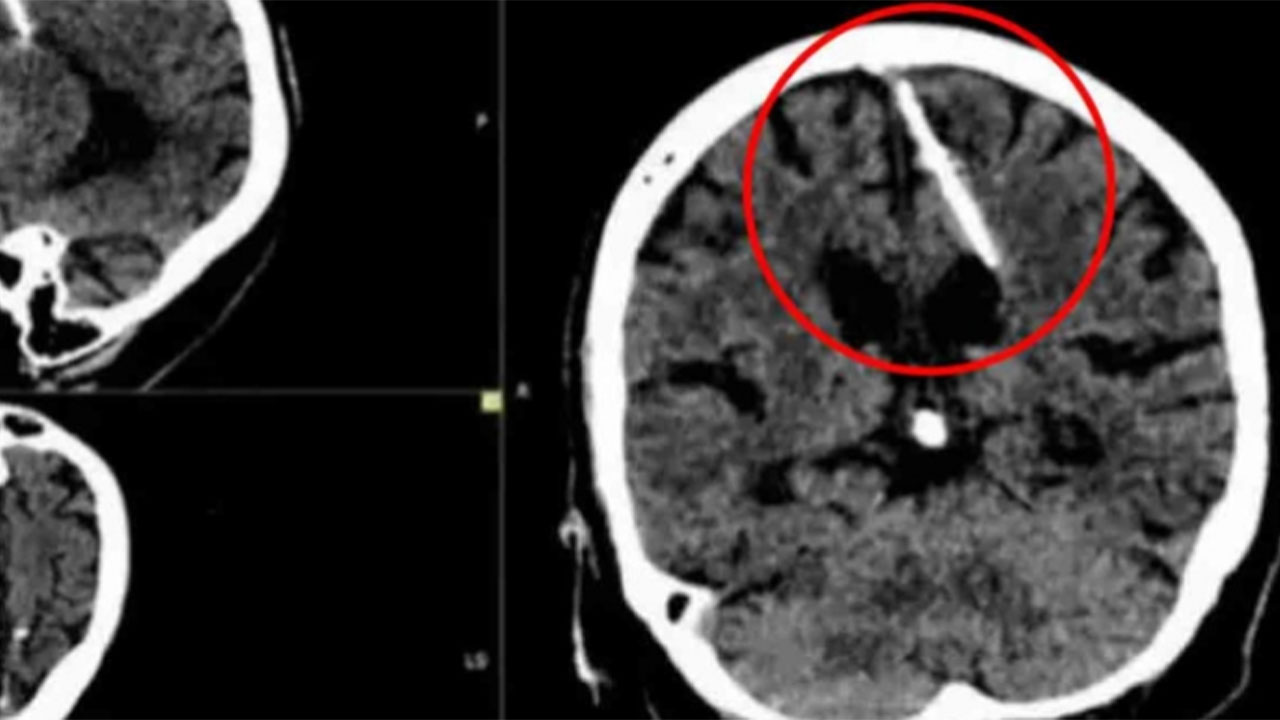

¡Qué locura!: mujer de 80 años descubrió que tiene una aguja en el cerebro desde su infancia

Una mujer de 80 años descubrió que tiene una aguja en su cerebro desde su niñez. Los médicos revelaron la posible causa del hecho.

Una mujer de 80 años acudió a un chequeo médico de rutina y se enteró que tiene una aguja en su cerebro.

El hecho ocurrió en un hospital de Rusia, en donde una radiografía de la mujer de 80 años reveló el peligroso objeto.

Se trata de una aguja de tres centímetros, la cual estaba ubicada en el lóbulo parietal izquierdo de la mujer.

Para su sorpresa, la aguja estuvo en su cerebro desde su infancia, sin embargo, está nunca le ha causado dolor.

En una hipótesis, los médicos indicaron que la mujer pudo ser utilizada en una práctica que realizaban los padres durante la Segunda Guerra Mundial.

Durante los tiempos de guerra, los padres introducían una aguja en un punto blando del cráneo de los recién nacidos.

Este punto se cerraba y ocultaba la aguja, provocando la muerte del bebé.

Pese a que la aguja ya había sido descubierta, los médicos decidieron no sacarla debido a la avanzada edad de la mujer.

Apuntaron que la aguja no representa un peligro inmediato para su salud, dado que ha vivido con el elemento desde su niñez.